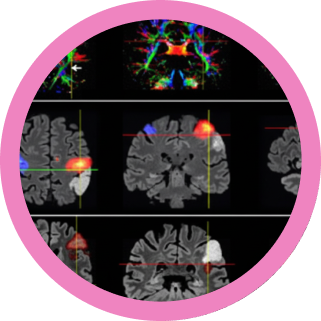

La Resonancia magnética funcional ( RMf) es la herramienta que nos permite comprender cómo la física de la resonancia magnética se une a la fisiología cerebral para detectar cambios minúsculos en el flujo sanguíneo, los cuales son el eco de la actividad neuronal. Además se aprenderá cómo se adquieren y se procesan estos datos para generar mapas de funciones cerebrales.

Los estudios de Resonancia Magnética Funcional (fMRI) son parte esencial de la planificación y el abordaje en casos clínicos pre-quirúrgicos en neurocirugía. En esta clase se pretende dar una base teórica para entender la utilidad y aplicación actual de estos estudios. Comprenderemos qué partes del cerebro se activan y para qué se usa esta poderosa herramienta en la investigación y en la práctica diaria.

-Interpretar mapas de activación cerebral y patrones de conectividad funcional.